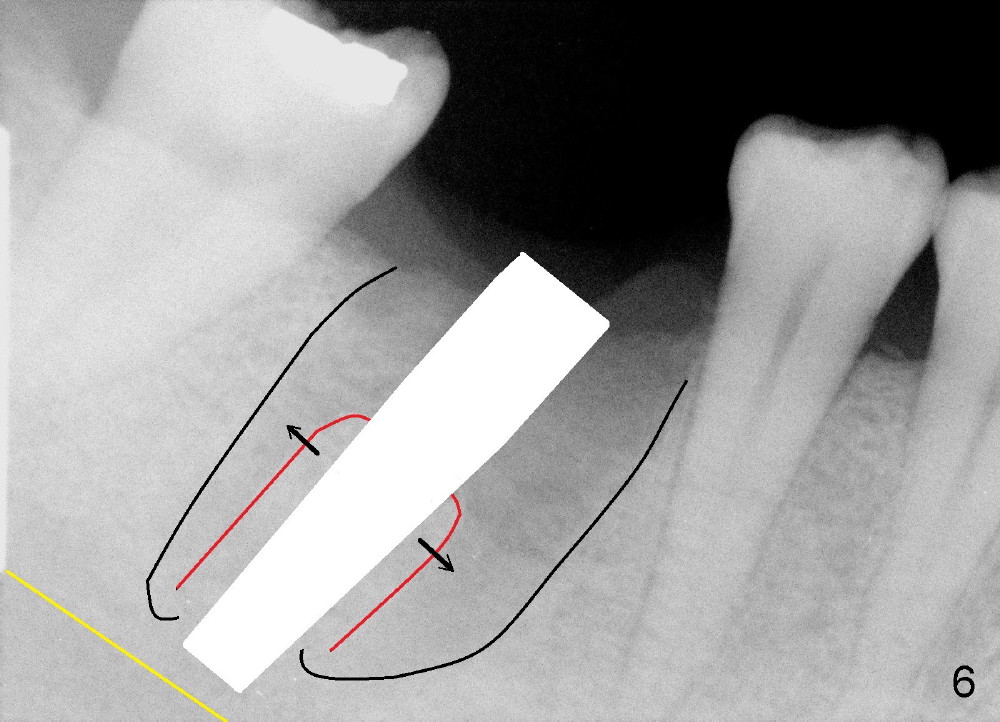

A 43-year-old lady had the lower right first molar extracted in other office last month. The socket appears to be healing normally (Fig.1). Tatum tapered implant 6x17 mm is planned (Fig.2). The implant is to be placed inside the septum (Fig.3 red outline; black: mesial and distal sockets; yellow: the upper border of the inferior alveolar canal). Either 1.5 mm pilot drill or 2 mm RT is used to start osteotomy in the septum at the depth of 17 mm (Fig.4 white outline). The osteotomy is enlarged with alternating use of osteotomes and 17 mm series tapered drills or Bicon reamers if autogenous bone will be needed (Fig.5 black), while the septal bone is pushed mesiodistally (arrows). After application of taps, an appropriately sized implant is placed (Fig.6 white). The septal bone continues expanding (arrows), whereas the mesial and distal sockets are being decreased.

The axis of osteotomy and of the implant is not consistent with that of the 2nd premolar. Instead it is more or less parallel to that of the 2nd molar. Intraop PA may confirm this observation.